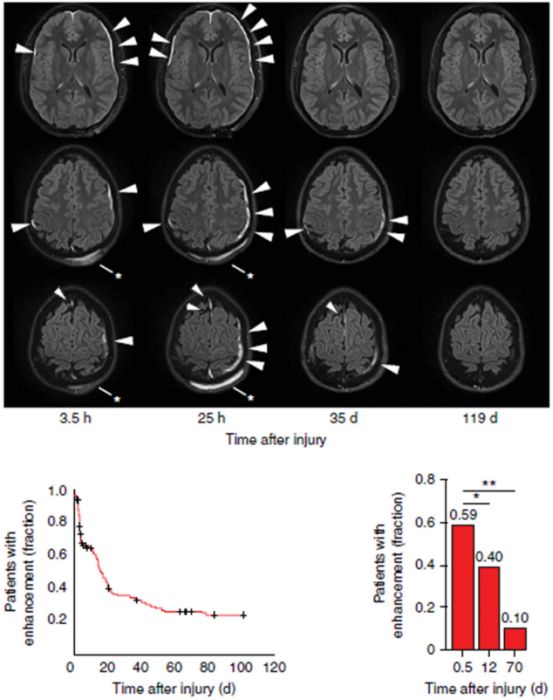

PMID: 30125028 DOI: 10.1093/neuros/nyy298

轻度创伤性脑损伤(mTBI)在临床上很常见,但mTBI的病理生理作用尚未完全阐明; 但在过去十年中发现慢性创伤性脑病(CTE)后,有些人可发生脑实质内的持续性损伤。最近在Nature Immunology上发表的研究揭示了mTBI后促进脑膜重塑和血管修复的一些特异性免疫反应。虽然脑膜和脑实质之间存在明显的生理和微环境差异,但这项工作可能会提供一些关于免疫反应如何受持续性损伤影响的推断,并可能解释mTBI中最突出的临床症状头痛的病理生理。